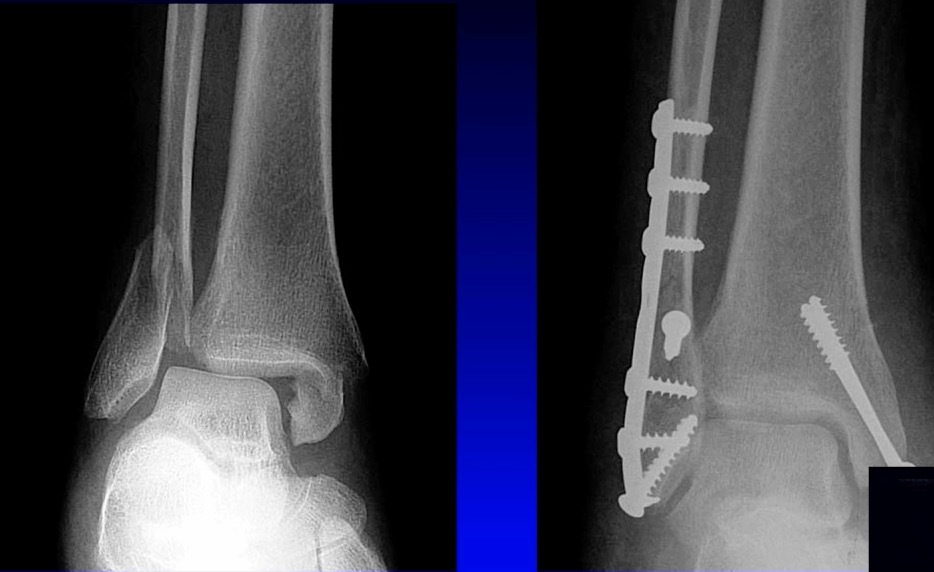

There’s much controversy in terms of should we wait or should we allow acute weight bearing following fixation of an unstable ankle fracture. Traditionally, patients were kept non-weightbearing for 6-12 weeks in some kind of cast or a boot. Nowadays, more contemporary approach is to allow earlier mobilization and protected weight bearing. Additionally, there’s many differences between North American and European schools of thought. When I give this talk to Europeans, they say “yeah we start immediate weight bearing all the time, that’s the standard.” But it’s certainly not the view in North America. I still see patients that have a beautiful x-ray with everything fixed and they’re kept in a cast for two months, which potentially defeats the whole point of surgical fixation. The benefit of surgery is to allow early mobilization and protected weight bearing. This practice can accelerate your patient’s return to work and return to life. However, nobody wants to see this x-ray in their clinic, especially with the staples still in (Figure 3).

This example is the fear that drives behavior amongst most orthopaedic surgeons who do not allow patients to move early.